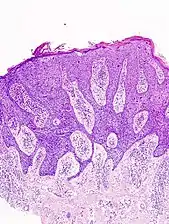

Histopathologically, the epidermis in cSCC in situ (Bowen's disease) will show hyperkeratosis and parakeratosis. There will also be marked acanthosis with elongation and thickening of the rete ridges. These changes will overly keratinocytic cells which are often highly atypical and may in fact have a more unusual appearance than invasive cSCC. The atypia spans the full thickness of the epidermis, with the keratinocytes demonstrating intense mitotic activity, pleomorphism, and greatly enlarged nuclei. They will also show a loss of maturity and polarity, giving the epidermis a disordered or "windblown" appearance.

Bowen's disease is essentially equivalent to and used interchangeably with cSCC in situ, when not having invaded through the basement membrane.[12] Depending on source, it is classified as precancerous[13] or cSCC in situ (technically cancerous but non-invasive).[47][48] In cSCC in situ (Bowen's disease), atypical squamous cells proliferate through the whole thickness of the epidermis.[12] The entire tumor is confined to the epidermis and does not invade into the dermis.[12] The cells are often highly atypical under the microscope, and may in fact look more unusual than the cells of some invasive squamous-cell carcinomas.[12]

In invasive cSCC, tumor cells infiltrate through the basement membrane. The infiltrate can be somewhat difficult to detect in the early stages of invasion: however, additional indicators such as full thickness epidermal atypia and the involvement of hair follicles can be used to facilitate the diagnosis. Later stages of invasion are characterized by the formation of nests of atypical tumor cells in the dermis, often with a corresponding inflammatory infiltrate.[12]